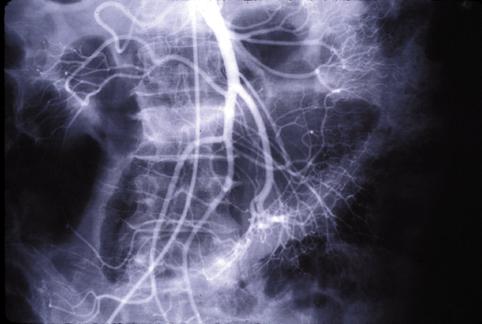

症例提示(所在地,施設名等): 東京都・ 国立がんセンター中央病院と九州がんセンターの共同作成

TIC症例

症例登録日 1999/01/01

画像数 39

性別 女性

年齢 55-59

画像ID:5428

[ 画像ID:5428 ]

■詳細データ

疾患(病理主体)の分類悪性リンパ系腫瘍/悪性リンパ腫

部位(臓器別)小腸/空腸

検査方法X-P

病変の最大径(ミリ)40以上

腫瘍の深達度s(a)